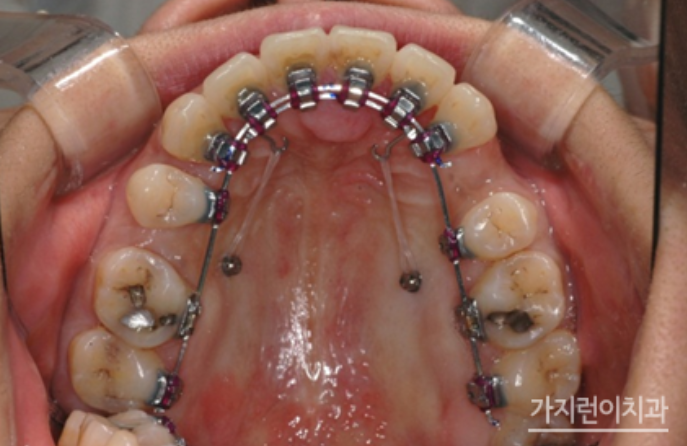

위 사진은 더블와이어를 이용한 설측탄댐장치인데요. 치아의 비뚤어짐이나 쓰러짐, 뿌리 조절 등을 정교하게 컨트롤할 수 있는 교정장치입니다. 3차원적인 치아이동 조절을 위해 특수하게 고안된 장치인데요. 기존의 설측교정장치가 뿌리 이동이 용이하지 않았다는 단점을 개선해 미세한 조절이 가능해졌다는 특징이 있습니다.

위 사진처럼 설측으로는 복잡해보이는 장치가 보이지만 이를 앙 다문 상태에서는 장치가 보이지 않는데요. 두 개의 와이어를 사용해 치아이동에 필요한 힘을 효과적으로 줄 수 있는데다 치아의 쓰러짐을 방지해 마찰력을 줄여 결과적으로는 치료기간이 크게 단축되었다는 것을 볼 수 있습니다. 게다가 덧니, 돌출입, 비발치 교정 등 기존 설측교정장치보다 빠르고 탁월한 결과를 얻어볼 수 있겠습니다.